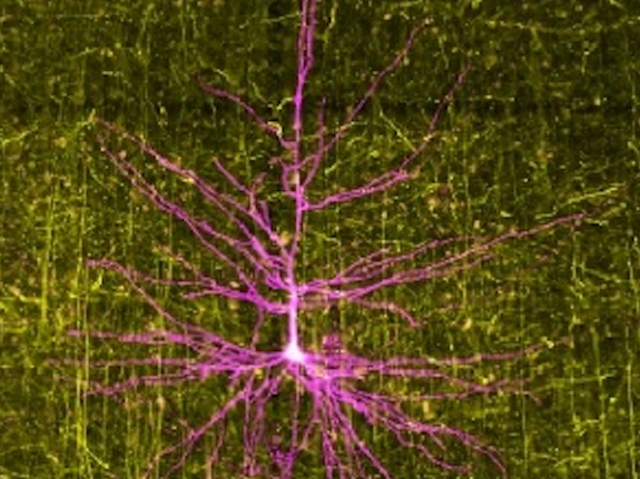

Tumours and Seizures

Seizures – a sudden excessive brain activity changing behaviour – are commonly triggered in patients with brain tumours, but why has been unclear. Here, looking at features, including synaptic activity (connecting to other neurons) and gene expression, of pyramidal neurons around brain tumours differences are found between patients with and without seizures. Using a mouse model, alterations in neurons called paroxysmal depolarizing shifts were identified as a potential biomarker for seizure risk